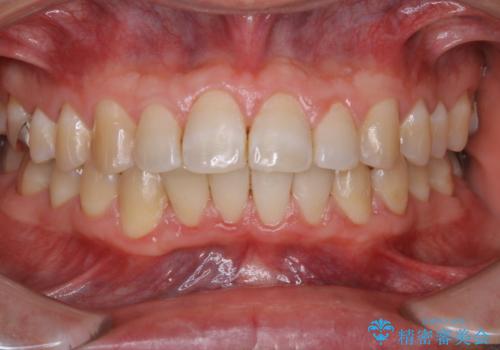

全体的にプラークや歯石が付着していて、歯肉炎が見られました。

状態に合った専門的な器具を使用して、歯質や歯肉へのダメージを抑えながらPMTC(自費クリーニング)60分コースを行いました。矯正治療後の保定装置がワイヤーの場合、フロス・糸ようじが通せないこと、歯ブラシがしずらいことなどにより、歯石プラークなどが付着しやすくなります。そのため専門的な器具による細かいケアを行うことがとても大切です。